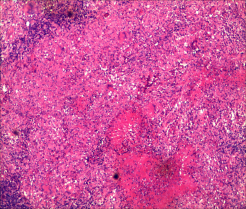

1.常规病理诊断(病理组织形态特征):结核病是一种特殊类型的慢性肉芽肿炎,基本病理变化:渗出、增生、坏死,典型病变形成结核结节,结节中心为干酪样坏死,坏死周边围绕类上皮细胞、散在多少不等的

Langhans巨细胞,结节外侧为淋巴细胞及少量反应性增生纤维母细胞。